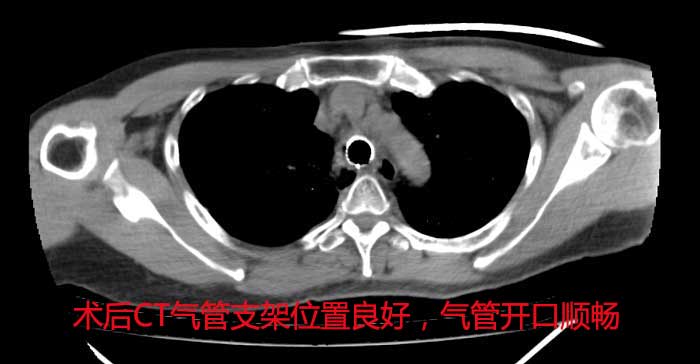

11月患者出现咳嗽、气喘,伴有严重喘憋、呼吸困难。入院后,经CT检查发现患者最狭窄的地方是组织气管的上段,直径仅为正常成人的1/4,整个肺部通气功能受到限制,不及时处理容易造成严重的呼吸衰竭和肺部感染。时间就是生命,黄德良主任带领医疗团队,紧急制定手术方案,争分夺秒进行气管支架置入术,置入支架来支撑气道、扩张狭窄段。凭着娴熟的技术,克服了技术难度高,风险大的问题,目前患者病情得到平稳控制,转入病房作进一步治疗。

广州圣丹福医院为国内熟练开展此项技术的为数不多的医院之一,手术的成功实施,克服了气管重度狭窄的医疗难题,为患者带来了生命的光明。